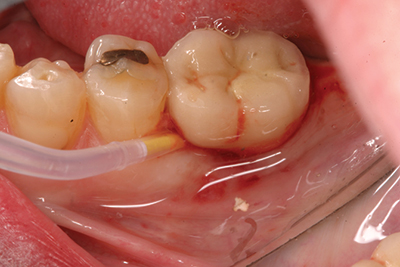

Treatment of peri-implant mucositis can often be accomplished via nonsurgical mechanical therapy. Although systemic antibiotics have been shown to reduce inflammation associated with peri-implant gingival tissue, as a monotherapy, they have been shown to be ineffective due to the bacterial recolonization of the implant surface without mechanical debridement.(12) Studies show that proper scaling and root planing with attention to bacterial plaque removal can be effective in reducing peri-implant mucositis lesions.(13) Localized drug delivery has also shown to have a positive effect in reducing mucositis lesions in conjunction with mechanical debridement (Fig. 2), especially in the areas of the mouth that are hard to reach.(14) After nonsurgical intervention, the patient should be recalled within three weeks. If no resolution of the inflammation has occurred, surgical intervention should occur.(15)